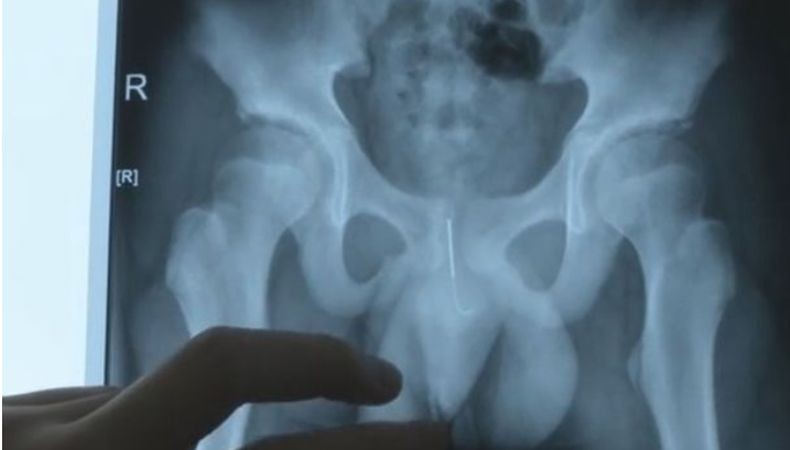

Remaja di China sengaja masukkan jarum 10 cm ke alat kelamin (Foto: AsiaWire)

WEINAN, iNews.id - Ada-ada saja ulah remaja 13 tahun di Kota Weinan, Provinsi Xi'an, China ini. Maksudnya baik, rapi caranya salah. Dia memasukkan jarum akupuntur sepanjang sekitar 10 sentimeter ke alat kelamin dengan tujuan agar tak tertidur saat mengerjakan PR.

Dia dirawat di Rumah Sakit Anak Xi'an untuk selanjutnya menjalani operasi pengangkatan jarum.